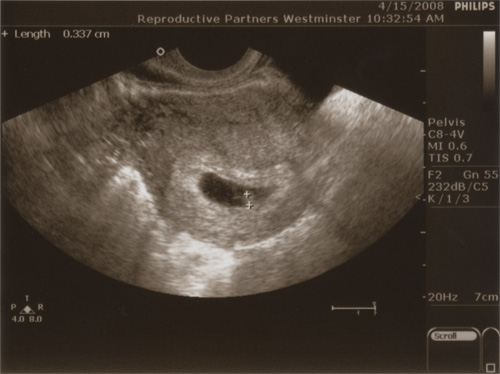

On Tuesday morning, as Linda mentioned, we had our second follow-up ultrasound (the next one is in two weeks). The stated purpose was to see a “heartbeat” — defined loosely by our doctor as a couple of lines wiggling.

It was very hard to see, to be honest, but there was definitely something moving in the picture. The egg sack was much bigger, and the bump of the uterus was taking up a lot more space in there, as expected. We were very very happy, as you can imagine.

Hm, maybe I was looking at the wrong place for a heart beat after all. I wasn’t looking at the area outlined by the two marks–I think that’s the yolk sac?–but at the line next to the yolk sac. Is the heart beat in the yolk sac? That doesn’t make sense…I’m confused! (Clearly this heart beat was a tricky thing to see!) 🙂